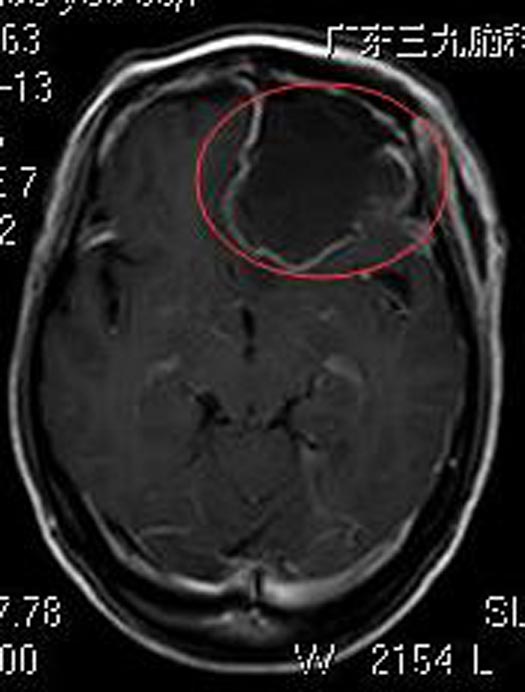

知道检查结果,儿女们吓出一身冷汗,赶紧陪着母亲来到广东三九脑科医院。进一步头颅MR 检查显示:前颅窝底左侧占位病灶,病灶范围约53.2mm×37.8mm×43.1mm,考虑脑膜瘤可能性大。

家属要求手术治疗,经评估无手术禁忌症。综合神经外科鲁明主任主刀,在全麻下行冠状开颅左侧蝶骨平台脑膜瘤切除术,术中显微镜下见肿瘤呈灰白色,鱼肉状,质韧,边界较清,血供丰富,予镜下将肿瘤顺利全切除。术后病理结果提示:砂粒体型脑膜瘤 WHO I级。